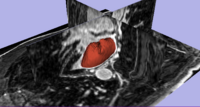

Prostate SegmentationThe 3D prostate MRI images are collected by collaborators at Queen’s University. With a little manual initialization, the algorithm provided the results give to the left. The method mainly uses Random Walk algorithm. More... New: Y. Gao, R. Sandhu, G. Fichtinger, A. Tannenbaum. A coupled global registration and segmentation framework with application to magnetic resonance prostate imagery. IEEE Trans. Medical Imaging, volume 29, 2010, pp. 1781-1794. |